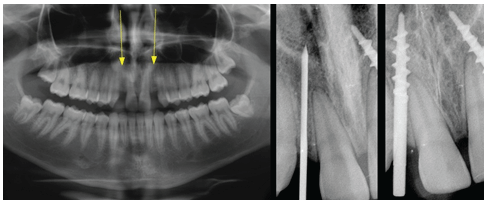

Figure 3: The radiographs: 1 that shows the remaining bone volume. The Pasqualini self-centering burr, which allowed to make an osteotomic tunnel specific for the implant insertion. Two bicortical screws (3.5 mm in the spire) at the end of the procedure.

Figure 7: X-rays show two implants properly set in the bone, which appears to have minimal thickness.